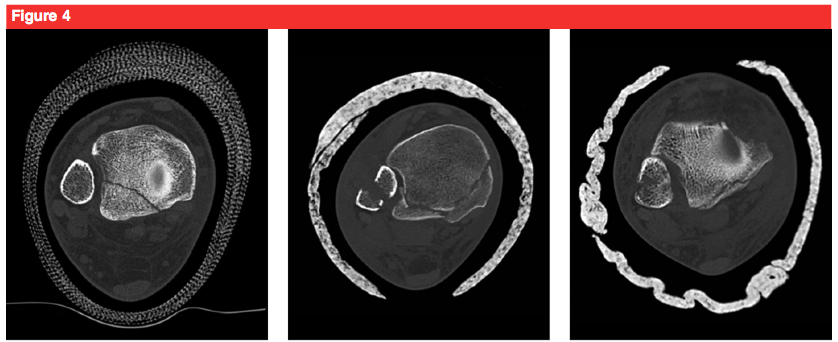

6 features of sacral dysmorphism

High sacral body (in line with iliac crests)

Mammillary bodies (underdeveloped TPs)

Enlarged, asymmetrical sacral foramina

Tongue-in-groove SI joint on axial CT

Sacral disk visible

Anterior alar indentation seen on inlet view